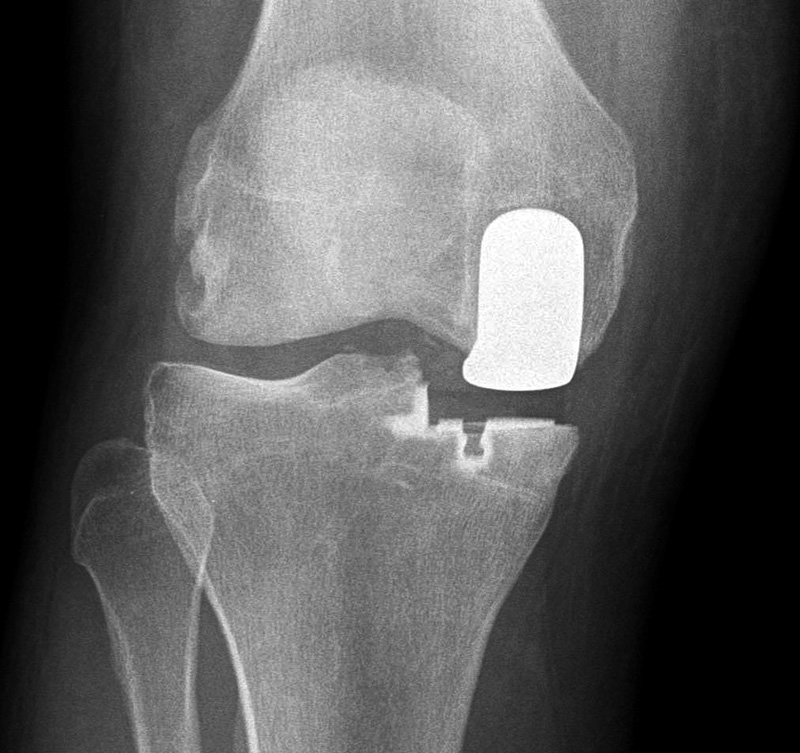

| Unicompartmental knee prosthesis placed in the medial compartment (AP view) |

Unicompartmental knee prosthesis placed in the medial compartment (lateral view) |

Unicompartmental knee prosthesis placed in lateral knee compartment |

50 year-old man with lateral knee compartment degenerative osteoarthritis |